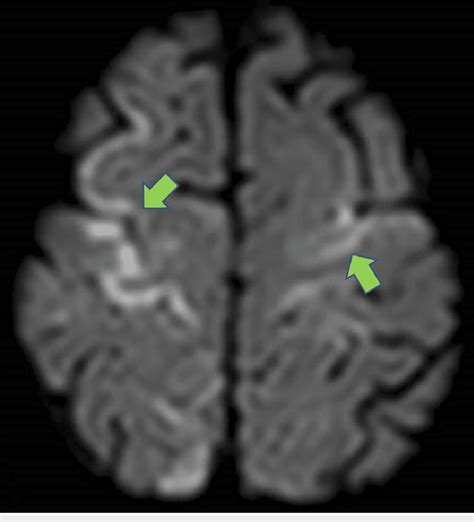

Interpreting DWI Scans: What to Look For

Interpreting Diffusion-Weighted Imaging (DWI) scans can seem a bit daunting at first, but once you understand the basic principles, it becomes much clearer. The most critical thing to remember is that restricted diffusion appears bright on DWI images . Why bright? Because the sequence is designed to attenuate the signal when water diffuses freely, and preserve the signal when diffusion is restricted. So, areas where water molecules can’t move easily – due to swollen cells, tightly packed structures, or other microstructural changes – will stand out as hyperintense, or bright, spots. The most classic example is an acute ischemic stroke . In the early minutes to hours after a stroke, brain cells become damaged, their cell membranes lose integrity, and water rushes in, causing them to swell. This swelling severely restricts the movement of water molecules. Consequently, the affected area lights up brightly on the DWI scan. This is often the very first sign of a stroke visible on MRI. However, it’s crucial to distinguish true restricted diffusion from other phenomena that can also cause bright signals. One important consideration is T2 shine-through . Some tissues naturally have a long T2 relaxation time, meaning they appear bright on conventional T2-weighted images. If these tissues also have some degree of diffusion, their signal might still appear bright on DWI, even if diffusion isn’t truly restricted. This is where the ADC map comes in as your best friend. Remember, the ADC quantifies the actual rate of water diffusion, independent of T2 effects. In areas of true restricted diffusion (like a stroke), the ADC values will be low . In contrast, areas that are bright on DWI due to T2 shine-through will have normal or even high ADC values. So, the combination of a bright DWI signal and a corresponding low ADC value is the hallmark of restricted diffusion and strongly suggests a pathological process like stroke or cytotoxic edema. Another important interpretation point is anisotropy . In tissues like the white matter of the brain, water diffusion isn’t the same in all directions. It tends to follow the direction of the nerve fibers. Multi-directional DWI and ADC tensor imaging can reveal these directional differences, which are crucial for understanding the integrity of white matter tracts. For instance, conditions that damage these tracts, like multiple sclerosis or TBI, can alter the pattern of diffusion. In tumors, DWI can help assess cellularity. Highly cellular tumors often exhibit restricted diffusion (bright on DWI, low ADC), which can help differentiate them from less cellular tumors or other lesions. So, when you’re looking at a DWI scan, always look at the DWI image and the ADC map together. The DWI highlights potential areas of concern, and the ADC map helps confirm whether the signal change is due to true diffusion restriction or something else. It’s this combined interpretation that makes DWI such a powerful diagnostic tool.